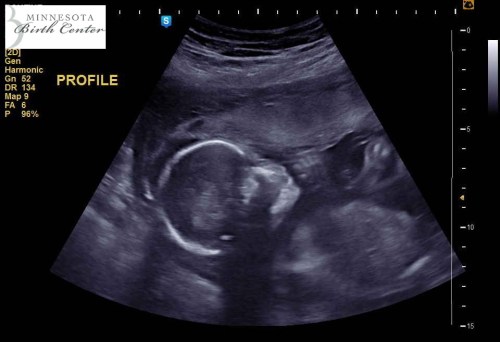

I looked over and saw this:

Amazing work, child.